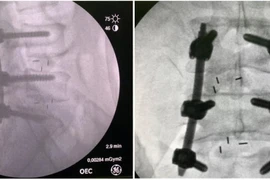

(khoahocdoisong.vn) - Thay vì mổ bằng tay với vết mổ lớn, lần đầu tiên tại tuyến tỉnh bệnh viện Đa khoa Phú Thọ đã tiến hành phẫu thuật bắt vít cột sống bằng robot. Công nghệ này không chỉ giúp giảm đau cho bệnh nhân mà độ chính xác cao tránh tổn hại dây thần kinh.